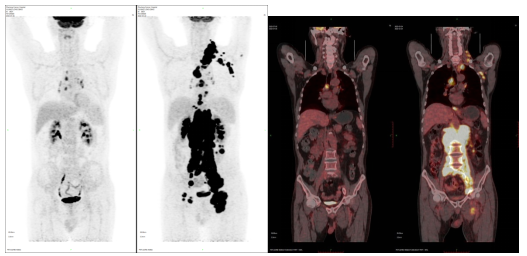

PET-CT分子影像诊断